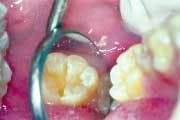

Since the introduction of fluoridation, outwardly detectable decay has been dramatically reduced. Because of the strengthening that fluoride creates in the outer layer of tooth enamel, the pattern of decay has changed. Rather than large areas of a tooth surface succumbing to the attack of plaque acid, decay now appears as small discreet areas, often undetectable to the dental probe, yet visible as a color change inside the tooth under magnification. Dentists have observed this change, and have continued to develop a science based on prevention and protection and the continuing miniaturization of all treatment procedures. New filling and restorative materials and techniques also have been developed. The new techniques require early and aggressive investigation of stains, the targeted removal of unsound tooth structure vs. the indiscriminate removal of sound tooth structure, and bonded restorations rather than traditional "drill, fill, and bill" approaches.

Patients are showing a great demand for conservative dentistry. Micro air abrasion has opened up a whole new method of treatment for them that preserves far more tooth structure than was ever previously possible. The resulting surfaces also are better prepared to receive and retain bonded restorations, compared to previous traditional methods of preparation.